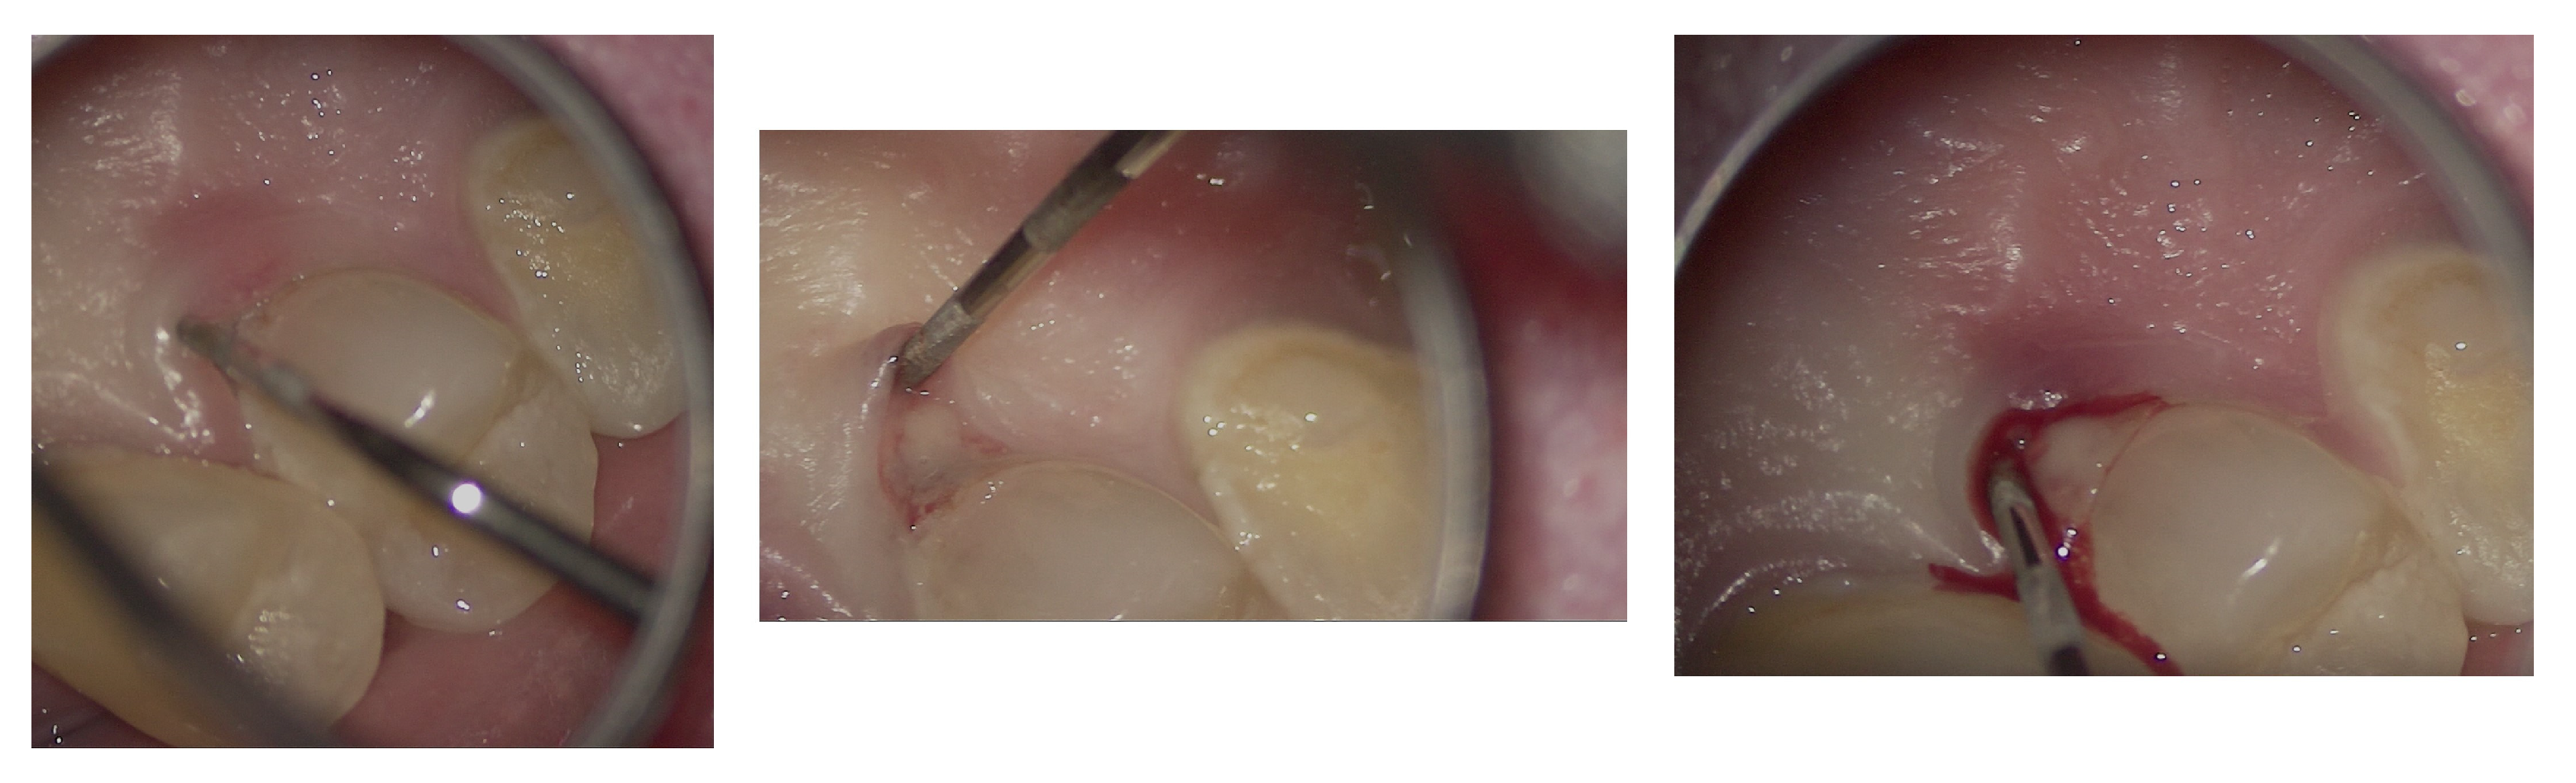

The entire procedure was performed under an operating microscope, Zumax 2380®, with an integrated HP camera (Zumax Medical Co., Ltd., Suzhou, China). In this case, the endodontic access cavity was prepared using a minimally invasive approach, aiming to preserve as much dental tissue as possible while ensuring adequate control and access to both the root canals and the cervical resorption lesion (Figure 6 and Figure 7).

Figure 6.

Microscopic exploration and probing of EPL under the operating microscope.

Figure 7.

Access cavity prepared under microscopic vision, highlighting the balance between preservation of dental tissue and achievement of adequate access to the root canal system and the lesion. (A) Opening and refinement of the cavity and access to the root canal system; (B–D) Irrigation phases with visible effervescence. Following the progressive definition and assessment of the extent of the access cavity to the resorptive lesion, the following can be observed: (E) Presence of inflammatory tissue within the cavity; (F,G) Debridement of the inflammatory tissue associated with root resorption; chamber and root canal system cleaned and sealed.